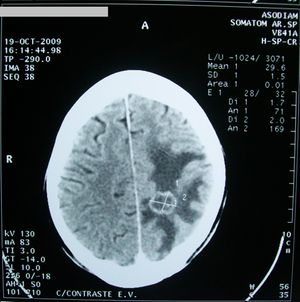

ويعتمد في المرحلة الثانية من التشخيص عادة على تصوير الدماغ (بالرنين المغنطيسي أو التصوير الطبقي المحوري).

إن الوذمة في (الشكل 2) موضعة في منطقة محدودة من الدماغ حول الكتلة الورمية، أما في حال كون الوذمة الدماغية معممة فعندها تُظهر الصور الدماغية إمحاء في الأثلام وأحياناً صِغراً في حجم البطينات الدماغية نتيجة انتباج النسيج الدماغي.

كثيراً ما تؤدي الوذمة الدماغية إلى ارتفاع الضغط داخل القحف، ويمكن قياس هذا الارتفاع ومراقبته بوساطة قثطار يوضع عادة ضمن البطينات.